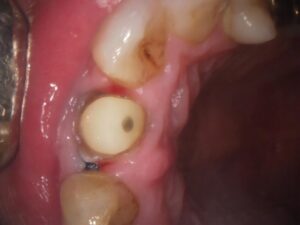

技工士が直接お口の中を確認(立ち会い)することで、隣の歯の色味や透明感、表面の細かな凹凸を正確に把握できます。写真だけでは伝わりにくいニュアンスを反映できるため、「どこを治療したかわからない」ほど自然な仕上がりが可能になります。

当院では被せ物の治療の際に、型取りの写真の共有や技工士さんの立会いを行うことで

より精度の高い被せ物を入れる取り組みをしています。